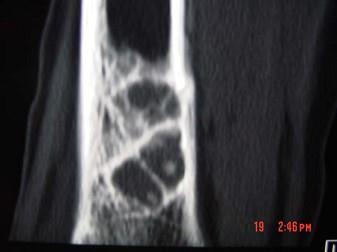

问题 男,30岁,感右小腿下段稍肿,其他无特殊,请结合所提供的图像,选择最佳选项 ( )

选项 A、良性骨肿瘤 B、纤维性骨皮质缺损 C、非骨化性骨纤维瘤 D、骨囊肿 E、骨结核

答案 C